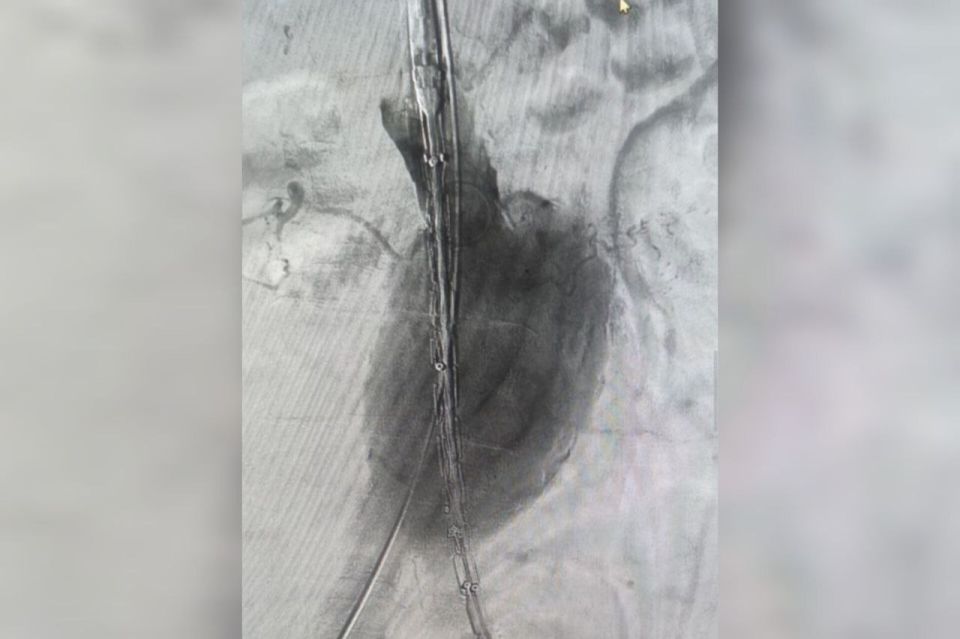

У пациента был крупный размер аневризмы, создававший высокую угрозу разрыва. Кроме того, мужчина старше 70 лет и имеет тяжелые хронические заболевания. Поэтому было принято решение провести операцию, хоть и крайне рискованную.Стент-графт укрепляет...